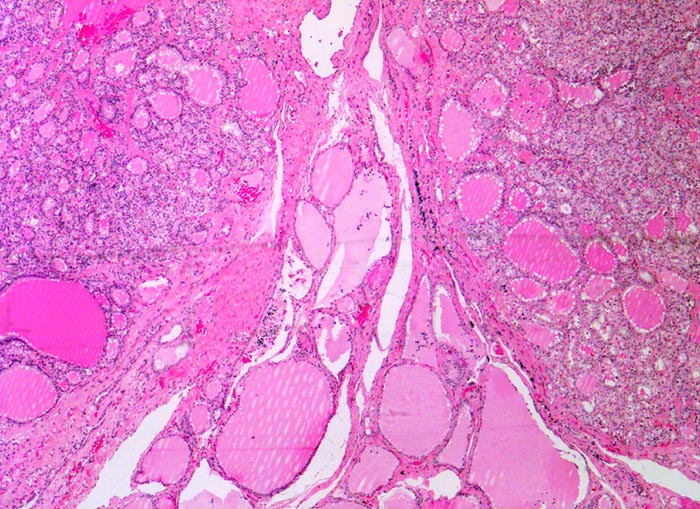

PathoPic – image database / PathoPic ID 4840 - autonomes Adenom

autonomes Adenom

benigner Tumor

Schilddrüse

Zwei scharf begrenzte überwiegend mikrofollikuläre Knoten mit morphologischen Zeichen der gesteigerten hormonellen Aktivität grenzen an atrophes makrofollikuläres Schilddrüsenparenchym in der Bildmitte.